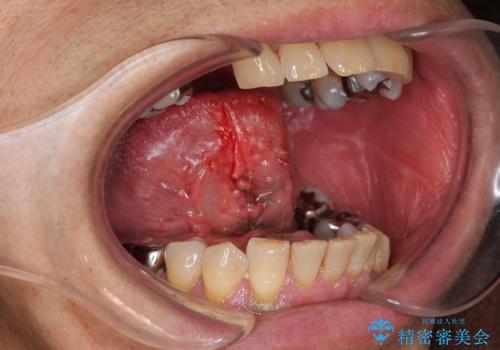

『舌小帯形成術』 ベロの動きを良くして滑舌を改善したい

- 舌の動きが制限され、滑舌を改善したい、と希望され来院されました。

舌小帯形成術を行うことで、滑舌の改善を図ります。形成術は約5分程度で終了し、1週間後に抜糸を行い治療は終了となります。

術後、舌の動きが改善され滑舌の改善を実感することができました。